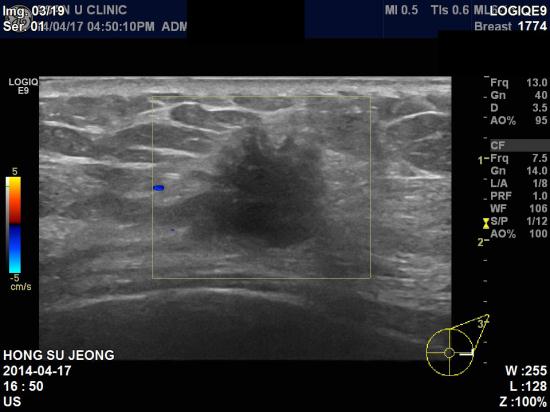

본원 초음파상 좌측 3: 30분 방향에

1.87 cm 의 불규칙한 경계를 가진 종괴 및 겨드랑이 림프절 비대소견있어

조직검사와 세포검사 시행결과 침윤성 유관암 및

겨드랑이 림프절 전이로 진단되었습니다.